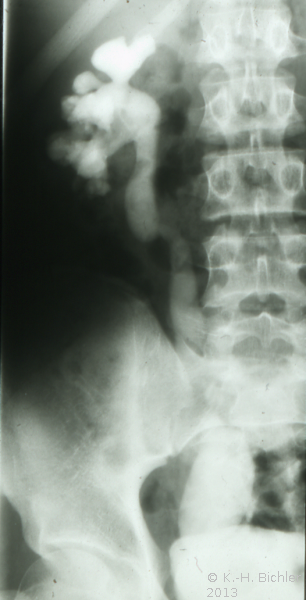

Bei dem 16 Jahre alten Jungen wurde aufgrund der ausgedehnten Ureterozele mit sekundärem partiellem Megaureter insbesondere Dilatation des Harnleiters und länger dauernden rezidivierenden Harnwegsinfekten eine offen Ureterozelenabtragung und Ureterreimplantation durchgeführt (Abbildung 7).